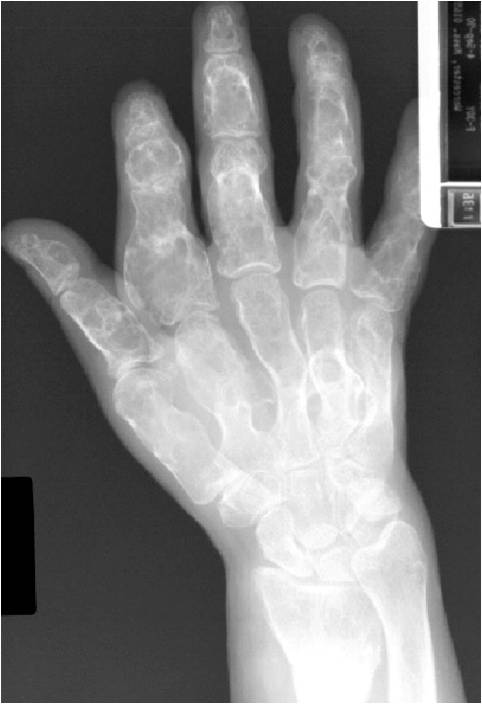

- 50% involve hands and feet (mostly phalanges)

- Cortex may be scalloped and thinned in the phalanges

- Geographic lytic lesion

- Expansile remodeling with thinned cortex

- Chondroid matrix with calcifications in majority of tumors

- Approximately 20% have limited or no calcifications

Enchondromatosis

- May be predominantly unilateral or affect a single extremity/limb

- Affected limb is often shortened and deformed and angulated

- Marked skeletal deformity

Enchondromas in enchondromatosis may involve the metaphysis, diaphysis, epiphysis and articular cartilage

- Hands and feet greatest involvement